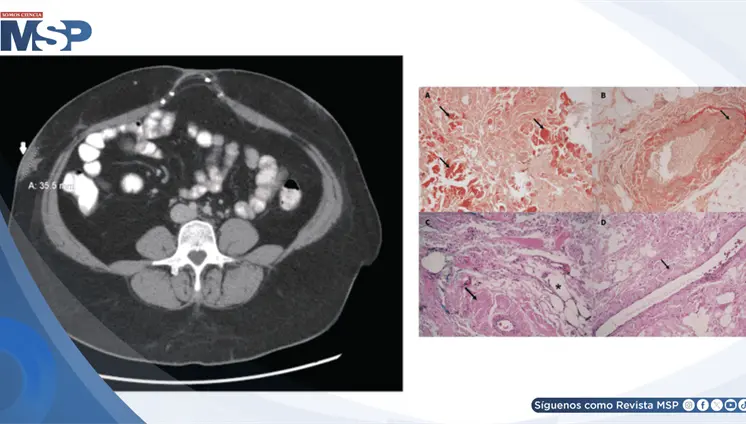

La mujer de 71 años, con antecedentes de histerectomía total y salpingooforectomía izquierda hace 30 años, presentó distensión abdominal progresiva y aumento de peso durante cuatro años.

Las imágenes mostraron una aorta abdominal significativamente dilatada, con un diámetro transversal de 4.4 centímetros, muy por encima del límite normal de 3 centímetros.

La paciente desarrolló simultáneamente un carcinoma mamario triple negativo de rápido crecimiento y un adenocarcinoma rectal invasivo, ambos confirmados como tumores primarios independientes.